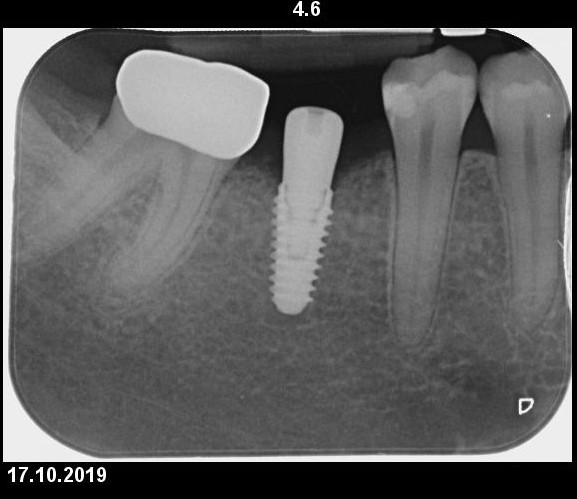

Implant Megagen Anyridge, inserat intr-o creasta atrofica, de 6,5mm latime. Simple anyridge implant placement, with bone expansion and CTG to compensate the 6,5mm bone crest.

Insufficient crest width and thin tissue